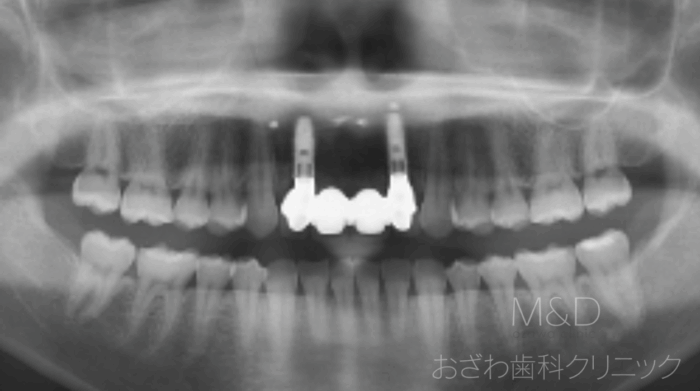

術後

治療内容

上顎前歯の抜歯、骨造成手術(GBR)

概算費用

骨造成費約20万円(税別)材料費含む、インプラント1本45万円

(仮歯代、ジルコニアボンド含む)